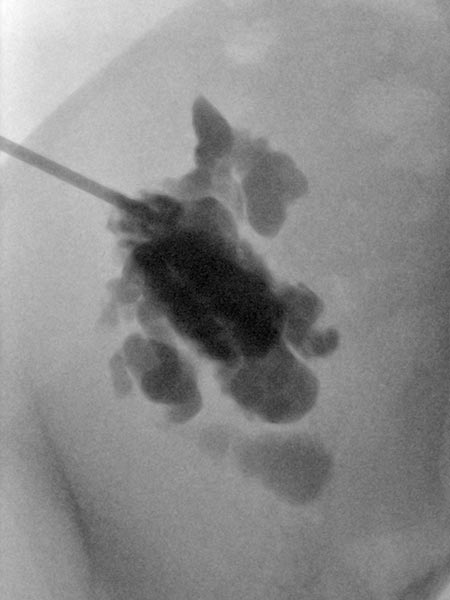

Ultraschallgesteuerte Punktion des zystischen Anteils der LM während der Sklerosierung. Über diese Punktionsnadel wird die LM zunächst kontrastiert, anschließend aspiriert und das Sklerosierungsmittel eingebracht.

Übersichtröntgenbild im Bereich der rechten Beckenschaufel nach Injektion von Kontrastmittel über die in der LM liegende Nadel. Es kontrastieren sich aus dieser Nadellage weite Anteile der LM, damit optimale Position für die Sklerosierung.